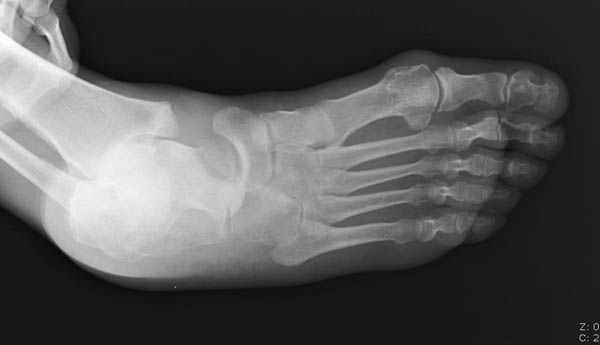

Уважаемые участники русского Ортофорума, поздравляю всех со всеми прошедшими праздниками: Новым годом, Рождеством, Hanukkah, Kwanzaa, желаю участникам всего наилучшего и здоровья.Повреждение таранной кости.Больной 81г автоавария, повреждение таранной кости, здесь снимки. Какие рекомендации?Djoldas Kuldjanov, MDDepartment of Orthopedic SurgerySt. Louis University Medical Center

Вдогонку по поводу перелома таранной кости, больная 81, не страдает диабетом, перелом закрытый, в первый же день поступления ограничились временным наружным фиксатором (как на снимке).

За пару недель насчитал 5 больных с переломом таранной кости, из них двое с двусторонним повреждением.

Примеры на снимке...